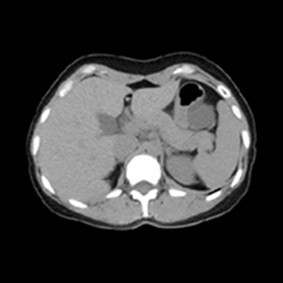

CT検査とは多方向からX線を照射し、身体の断面を撮影する検査です。

また、撮影した画像を重ね合わせることにより立体画像を構築し、より細かい診断ができます。

そして、CT検査では病変の存在、形態や性状などをより詳しく描出させるため、

臓器や血管にコントラストをつける造影剤という薬剤を用いて検査する場合があります。